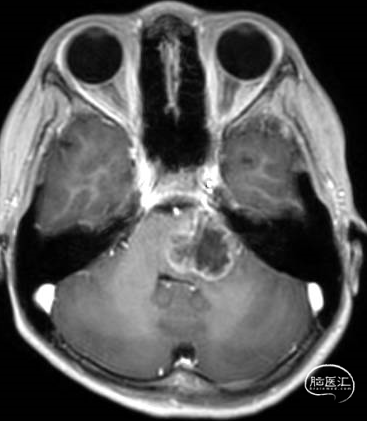

术前MRI

术后MRI